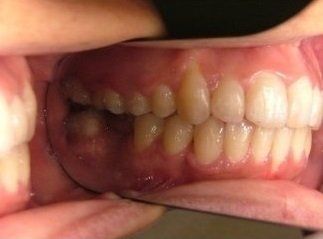

Il trattamento ortodontico non è solo per i bambini: se hai denti storti, affollati, mancanti o prominenti che ti impediscono di masticare e parlare liberamente, potrebbe essere necessario rivolgersi a uno specialista. L’ortodonzia prevede l'uso di apparecchi ortodontici, che possono essere fissi o rimovibili.

I dentisti studiano infatti le anomalie di costituzione, posizione e sviluppo di denti e ossa mascellari, e progettano l’apparecchio mirando al ripristino della corretta funzionalità dell'apparato masticatorio.